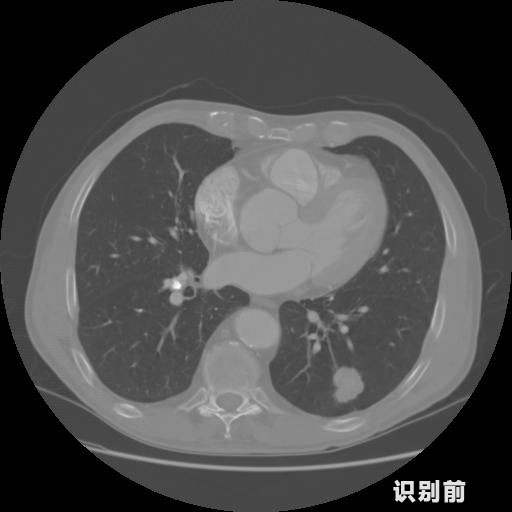

報(bào)告:

1.發(fā)現(xiàn)肺結(jié)節(jié)的可能性為95.56%---位于框指數(shù)位置:[331.70554 366.13406 365.21707 403.96234]